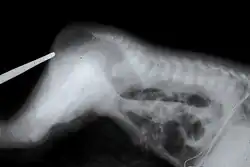

Es ist zu erkennen, dass der Dickdarm dabei blind endet, also der Anus fehlt.